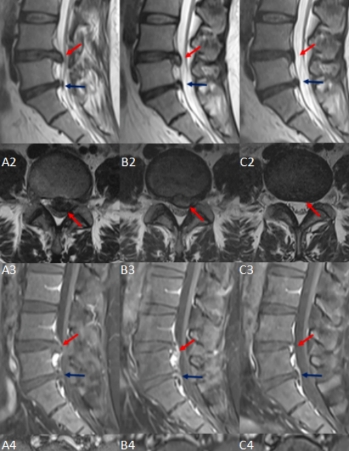

椎体夹心饼征!